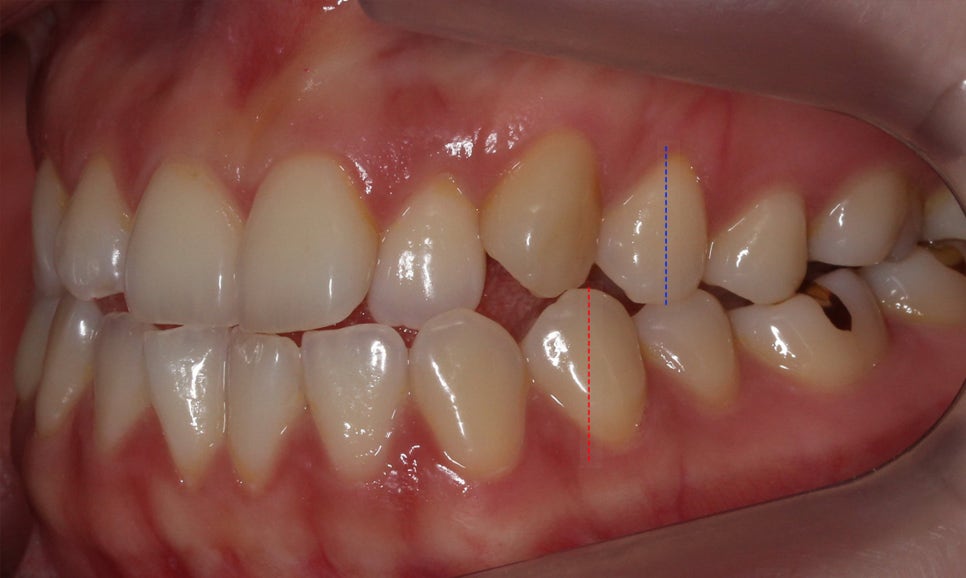

절단교합 교정 전 구내 사진입니다.

전치부를 보면 상악과 하악이

교합되는 부분에서 치아가 맞닿아 있는 모습인데요,

정상적인 교합 상태의 경우 상악이

하악의 윗면을 2mm정도 덮도록 교합됩니다.

(정중선도 변위되어 있는 모습)

증상을 더 자세하게 살펴보면

전치부 overbite 수치가 0에 가까운 모습으로

상악과 하악의 겹쳐지는 부분이 없습니다.

이러한 경우 많은 분들이 구치부의 부정교합을

동반하고 계시기 때문에 전체교정을 통해

부정교합 증상을 해소하는 것이 좋은데요,

절단교합 증상이 뚜렷하게 나타는

overjet 사진을 참고하여

발치 여부를 결정해야 합니다.